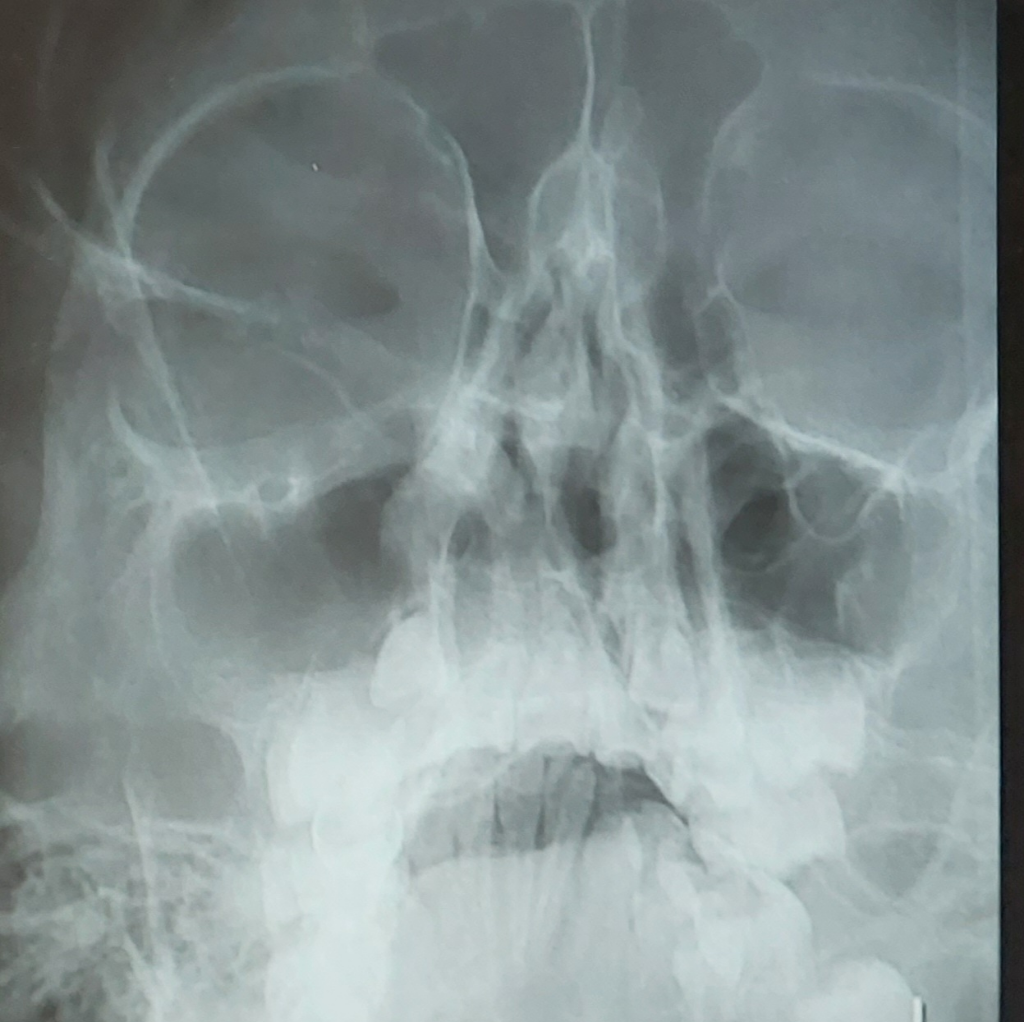

부비동 점막이 부어 있는건가요

농이 찬건지 부비동 점막이 부어 있는건지 알수 있을까요 오른쪽 부비동쪽이 좀 그래보여서요 확인 부탁드립니다.........

• 1번 째 사진

• 안녕하세요. 남희성 의사입니다.

저도 이비인후과가 아니라서 정확한건 모르지만 학생때 공부했던걸 기반으로 설명드리면 정상소견으로 보입니다.

이상소견은 아래 사진과 같이 부비동에 농이 차있는 속녀이 보이고 하얀색 액체가 차있는 모습을 확인할 수 있습니다.